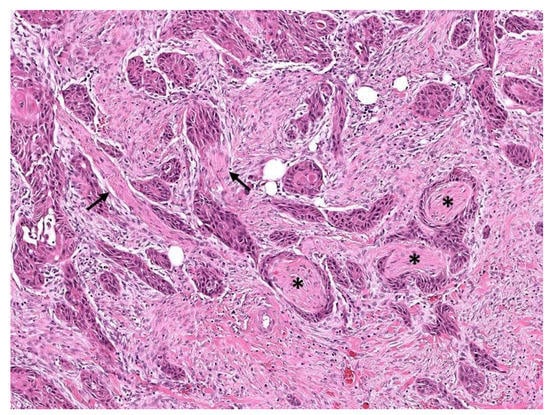

3. Perineurial Invasion

Abstract